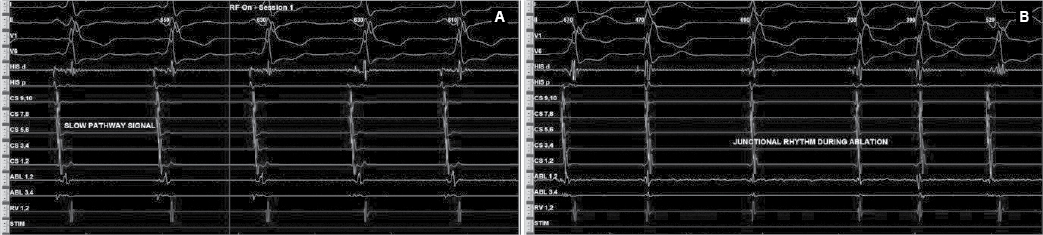

After written informed consent, patient was taken for electrophysiological study. Two quadripolar diagnostic catheters were advanced under fluoroscopy to His bundle region and right ventricular apex. One decapolar catheter was advanced into the coronary sinus. During the electrophysiological study at baseline, atrial-His bundle (AH) and His-ventricular (HV) intervals were 85 ms and 3 ms in sinus rhythm, respectively. There were no atrioventricular (AV) conduction abnormalities. A narrow complex tachycardia (tachycardia cycle length [TCL] = 400 ms) was easily induced during catheter placement with following features: initiation of the tachycardia with a critical AH interval, fixed 1:1 ventriculoatrial (VA) conduction, concentric retrograde activation with VA interval of 37 ms, a post-pacing interval (PPI, 576 ms)–TCL (406 ms) >115 (170 ms) and ventricular overdrive pacing resulted in a VAHV response. His synchronized and early premature ventricular contraction (PVC) did not reset the tachycardia. His synchronized premature atrial contraction (PAC) also failed to reset the tachycardia. The tachycardia was reproducible and consistent (Fig. 2). After confirming the diagnosis of typical AV nodal re-entrant tachycardia (AVNRT) a decision was taken for slow pathway ablation. Using a steerable ablation catheter, with the help of intracardiac electrograms (EGMs) and using fluoroscopy, the region of the slow pathway was identified. Radiofrequency applications were made in the region of the slow pathway while constantly monitoring temperature, impedance, ECG and intracardiac EGMs, monitoring for fast junctional conduction and radiofrequency energy was halted if there was evidence of VA block. Radiofrequency ablation resulted in a junctional rhythm with intact AV conduction, which is a typical response. The AV nodal slow pathway was successfully modified (Fig. 3).

Figure 3. Slow pathway signals (A) at rightward inferior extension showed fused signals because of underlying pathway. Junctional rhythm (B) in response of radiofrequency energy.